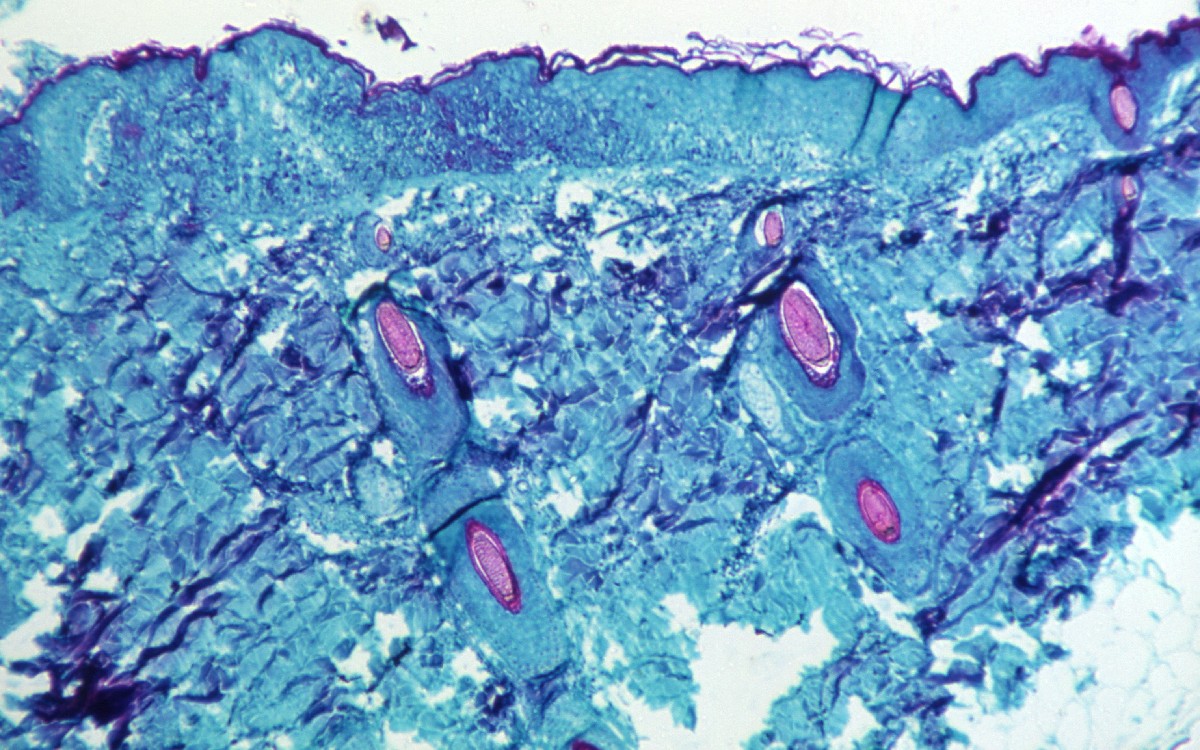

Asimismo, exhortó a los canadienses a conocer los síntomas de la viruela del simio e informar cualquier inquietud a su médico de cabecera. Los signos y síntomas de la viruela del simio generalmente pueden incluir fiebre, dolor de cabeza, dolores musculares, agotamiento e inflamación de los ganglios linfáticos, y una erupción que a menudo aparece unos días después de que se desarrollan síntomas como la fiebre.